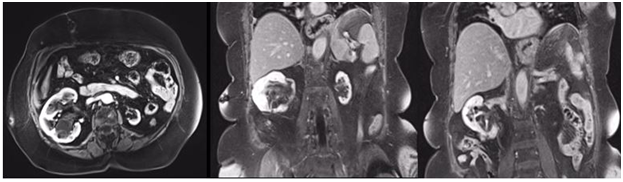

A 74-year-old female patient was referred to the urology department of a private hospital for a right kidney mass associated with left renal atrophy. She reported that symptoms began one year prior, starting with intermittent hematuria and lower back pain for three months. During an abdominal physical examination, the mass was palpated in the right renal store, with no other changes present. Upon laboratory analysis, it presented the following: hemoglobin (Hb) 13.0g/dl, Urea (Ur) 50mg/dl, Creatinine (Cr) 1.2mg/dl, and a glomerular filtration rate (GFR - MDRD) 46,68ml/min/1,73m2. A computed tomography (CT) scan of the abdomen revealed a hypervascular expansive formation of 10 x 11.2 x 6.8 cm, with exophytic and endophytic components, less than 1 cm away from the collecting system, centered on the anterolateral aspect of the kidney, exceeding the limit of the lower polar line by more than 50% (Figure 2), RENAL Nephrometry Score is 10x.

Figure 2 CT scan of the abdomen with contrast showing right tumor mass with the atrophic left kidney.